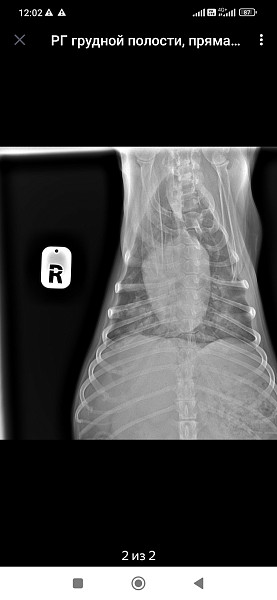

Добрый день!собачка кобель цвергпинчер 14 лет 10 месяцев,стал часто дышать,сделали рентген,помогите понять что с ним!

Ренген

Добрый день!ренген лёгких у собаки помогите прояснить ситуацию!сделали в связи с частым дыханием

Здравствуйте, у собаки выраженное затемнение по каудальным долям легких. Более всего это похоже на пневмонию.